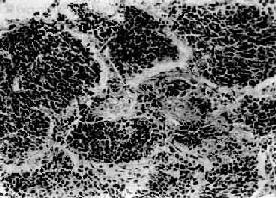

小细胞肺癌

图9-33 小细胞肺癌

短梭形癌细胞平行排列,群集成团(燕麦细胞型)